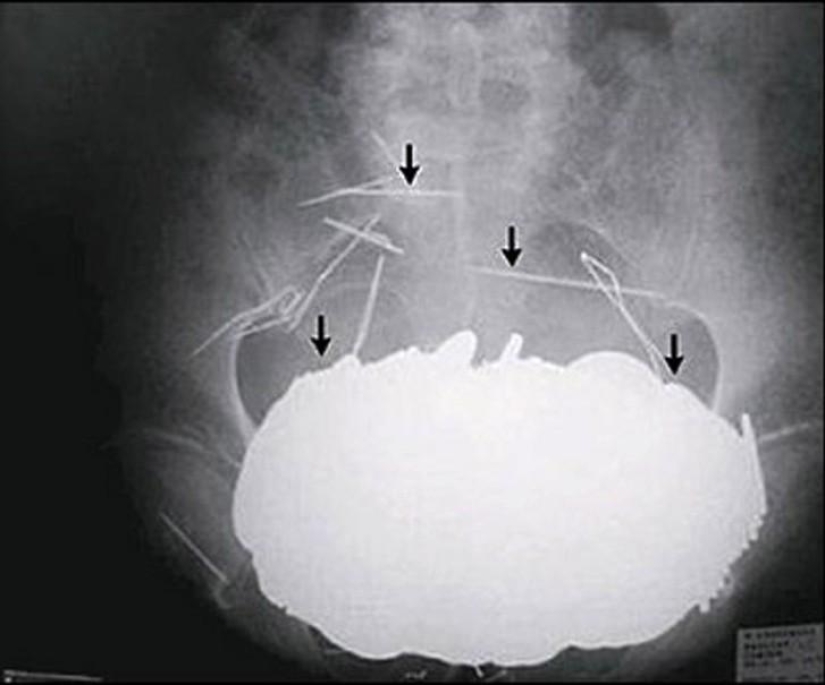

5. Magnets.